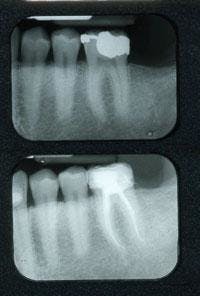

As a result of these discoveries, my fear of the pulp and dread of performing root canals are now distant memories (Figure 2). I now practice endodontics in fewer steps while achieving great results for my patients (Figure 3). Root canal treatment can and should be a part of every general practice. Endodontics is a procedure that is not only enjoyable, but satisfying and profitable as well. The phenomenal growth in endodontic technology and the myriad of resources available to improve our knowledge and simplify root canal procedures have paved new roads for the general practitioner. And with each new product that is introduced, endodontics will continue to become more simplified. If you have been avoiding endodontics in your office, maybe it’s time to start your own journey toward discovering endodontic ease. ■